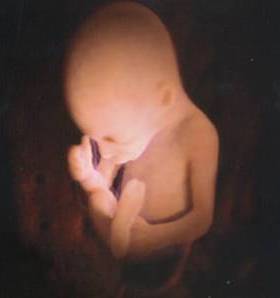

Il bambino ora prende quasi 200 grammi a settimana, pesa circa 1250 grammi e i suoi polmoni continuano ad esercitarsi nella respirazione. La testa cresce per fare spazio al cervello che ogni giorno vede nascere miliardi di nuovi neuroni, scalcia a più non posso ed è possibile contare i suoi movimenti per verificare il suo benessere e controllare che sia ben ossigenato. Per farlo, mettiti sdraiata su un fianco ogni giorno alla stessa ora, rilassati e concentrati su di lui, poi conta quanto tempo occorre al tuo piccolo per farsi sentire almeno dieci volte, conterai calci, pugni, singhiozzi e anche movimenti della testa e del sederino. La buona regola è che non servano più di due ore per arrivare a dieci.

Il bambino continua a crescere e ormai occupa quasi interamente lo spazio nell’utero.È possibile avvertire movimenti netti e precisi, al punto che potresti distinguere bene di quale parte del corpo si tratta, se la testa, il sederino o anche la schiena.

Il bambino è arrivato a circa 1400 grammi, è più cicciottello e la sua pelle è più liscia e rosea.Con le sue continue capriole, potrebbe trovare la posizione definitiva per la nascita.

Ora il piccolo pesa circa 1600 grammi, ogni giorno che passa mette su il grasso sottocutaneo e la pelle è meno rugosa, lo spazio disponibile è poco e i suoi movimenti sono meno “tellurici”.

L’utero è arrivato a circa 12 centimetri sopra la linea ombelicale trasversa e il piccolo pesa circa 1800 grammi ed è lungo circa 40 centimetri.

La peluria che lo ricopre comincia a scomparire mentre la vernice caseosa lo ricopre totalmente. Gli occhi distinguono la luce dal buio e, soprattutto, distingue il caldo dal freddo, al punto tale che si muove se viene posta una fonte di calore vicino alla pancia.